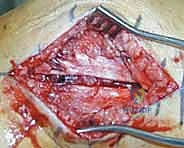

المرحلة الثانية: الفتح الجراحي والوصول للعظم

يستخدم الدكتور هطيف تقنيات الفتح الجراحي المحدود (Minimally Invasive Plate Osteosynthesis - MIPO) كلما أمكن ذلك، للحفاظ على التروية الدموية للعظم وتسريع الالتئام. يتم عمل شق جانبي بعناية للوصول إلى منطقة الكسر دون الإضرار بالعضلات المحيطة.

المرحلة الرابعة: التثبيت النهائي بالشرائح والمسامير (Fixation)

يتم استخدام "شرائح الإغلاق التشريحية" (Anatomical Locking Plates) المصنوعة من التيتانيوم عالي الجودة. هذه الشرائح مصممة خصيصاً لتأخذ شكل الجزء السفلي من عظم الفخذ. يتم تمرير الشريحة أسفل العضلات وتثبيتها بمسامير تغلق داخل الشريحة نفسها (Locking Screws)، مما يوفر ثباتاً ميكانيكياً هائلاً، حتى في حالات العظام الهشة.

المرحلة الخامسة: الإغلاق التجميلي

بعد التأكد التام من استقرار الكسر وحركة المفصل عن طريق الأشعة داخل غرفة العمليات، يتم إغلاق الجرح بطبقات متعددة باستخدام خيوط تجميلية لتقليل الندبات، ووضع أنبوب تصريف (Drain) لمنع تجمع الدم.